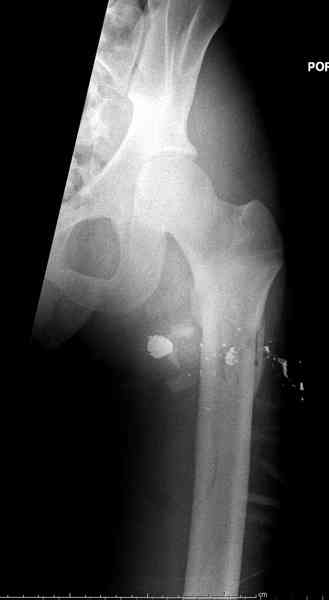

В нашем случае 21 летний боец уличного фронта, фиксацию провели на следующий день, зафиксирован интрамедуллярным штифтом. Не стали делать первичную хирургическую обработку точечной раны, зафиксирован как есть. Клинические снимки:

Вложение не в текстовом формате было извлечено…

Имя     : 2.jpg

Тип     : image/jpeg

Размер  : 15210 байтов

Описание: отсутствует

Url     : http://weborto.net:8080/pipermail/ortho/attachments/20081023/35009bb3/attachment-0010.jpg